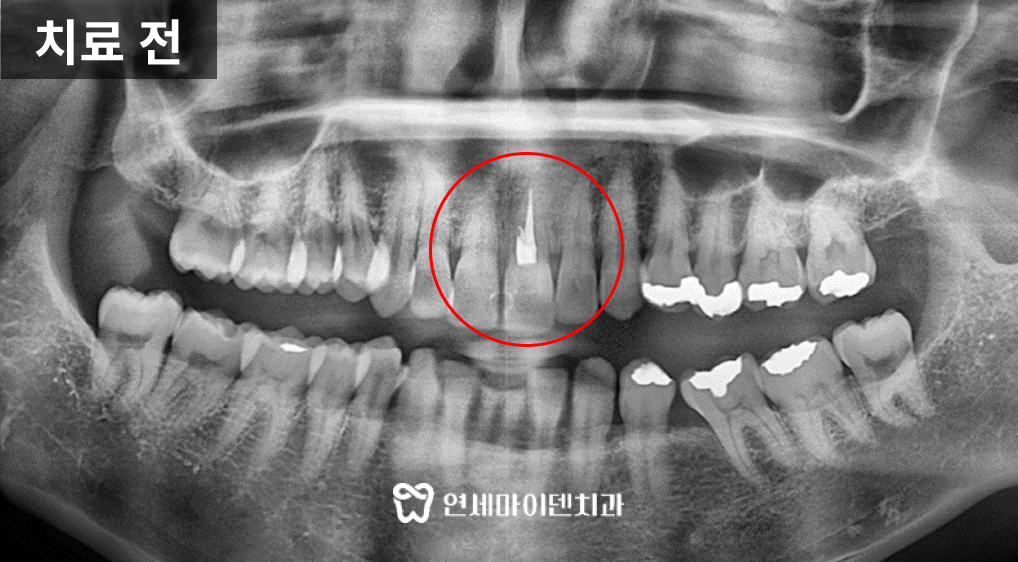

이 환자분은 위쪽 앞니에 불편감이 있어서 신경치료를 했음에도

계속해서 찌릿하고 시린 통증이 지속되어 저희 병원에 오셨습니다.엑스레이 상으로는 큰 염증이 확인되지는 않았지만,

녹은 잇몸 뼈의 양상이 좋지 않았습니다.이후 찍어본 CT 상으로 앞니 뿌리에 문제가 있는게 확인되었고,

발치를 하지 않으면 뼈가 계속 녹을 수밖에 없는 상황이었습니다.뼈가 많이 녹을수록 자연스러운 앞니 임플란트를 만들기 어렵기때문에

잇몸이 더 악화되기 전에 발치 즉시 임플란트를 진행하기로 하였습니다.앞니 임플란트 식립 시 중요한 것